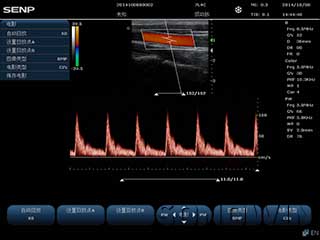

优质图像